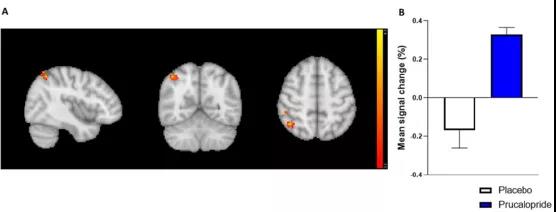

眾所周知,很多精神疾病常常伴隨著認(rèn)知功能障礙,認(rèn)知障礙不僅局限于記憶缺陷,還包括學(xué)習(xí)、注意力、語言以及處理速度等方面的障礙。這類障礙會(huì)對(duì)生活質(zhì)量產(chǎn)生相當(dāng)大的負(fù)面影響,所以迫切需要開發(fā)可以改善與精神疾病相關(guān)的認(rèn)知缺陷的治療方法。